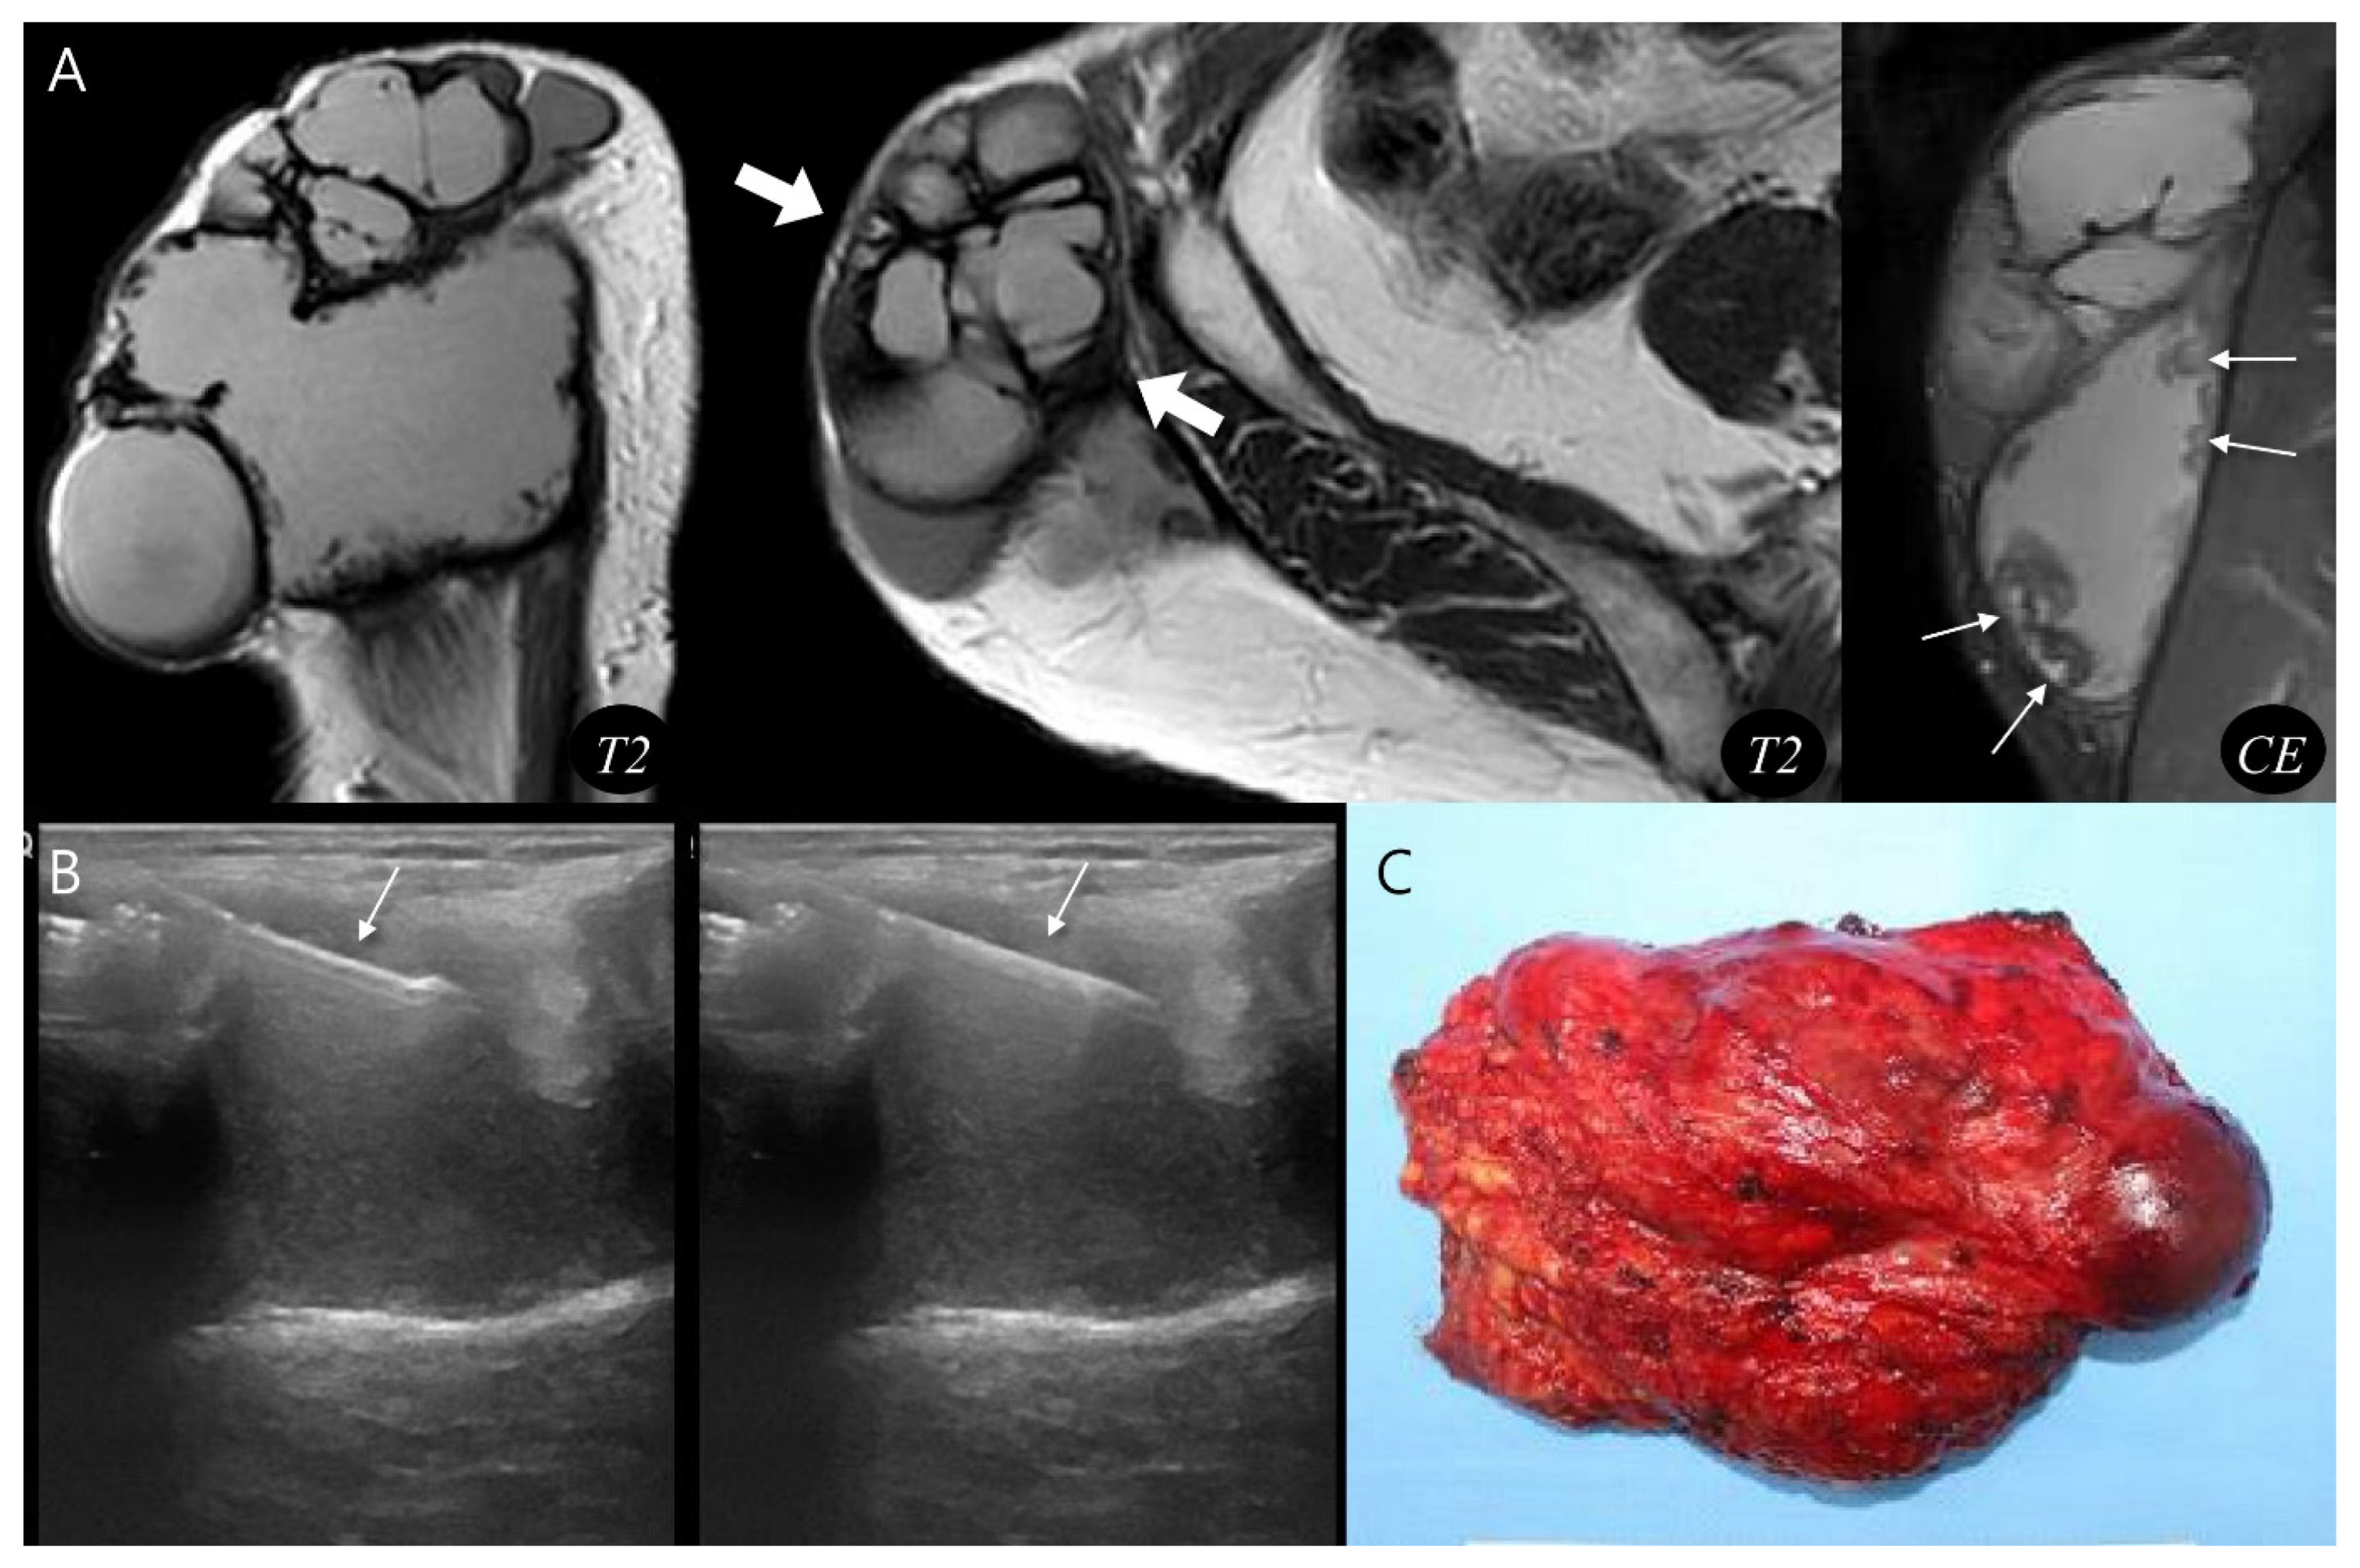

Figure 4.

Diagnosis and treatment of chronic expanding hematoma. (A) Sagittal and axial T2-weighted MR images demonstrate a multilobular, subcutaneous mass (thick arrows) with internal septations. The lesion shows peripheral nodular enhancement (thin arrows, granulation tissue) on coronal T1-weighted contrast-enhanced MR image. (B) Ultrasound-guided biopsy was performed using a core needle (arrows), confirming the hematoma. (C) Gross photograph of the wide excision demonstrates chronic expanding hematoma.